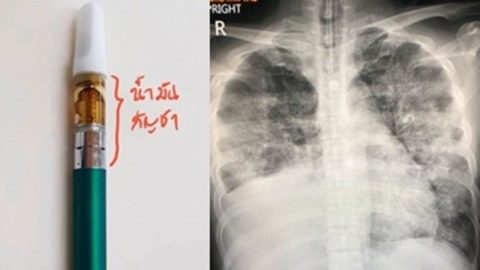

แพทย์เผย! พบผู้ป่วยปอดอักเสบเฉียบพลันจากการสูบบุหรี่ไฟฟ้า ผสมสารกัญชา